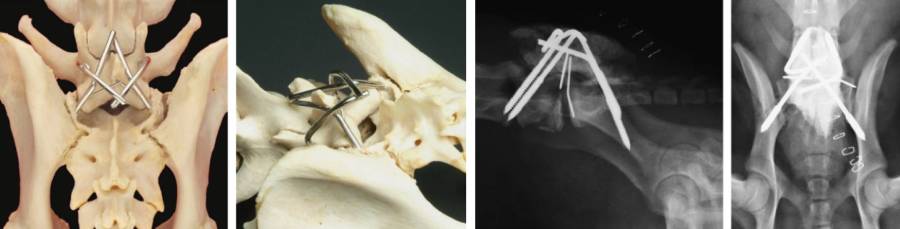

- Pinplatzierung L7

- Präparation zum Querfortsatz

- Vorbohrung

- im Winkel, wo der Proc. transversus zum Pedikel umschlägt

- 5-10° nach cranial

- 45° nach ventral

- Gewindepin platzieren

- Länge im vorhinnein am CT abmessen

- Pinplatzierung Sakrum

- Fasettengelenk freipräparieren

- direkt caudal vom Proc. articularis caudalis des L7 ins Sakrum bohren

- 45 ° nach ventral

- 45° nach caudal

- soll durchs Ilium gehen

- soll das Fasettengelenk zusätzlich sperren

- Pins verbinden

- Pins in die Mitte biegen

- mit Knochenzement verbinden